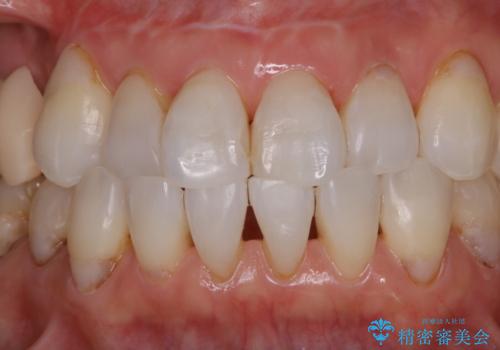

歯のクリーニングPMTC60分コース

- 色が気になるため、全体的にお口のお掃除を希望とのことで来院されました。PMTC60分コースを行いました。

毎日丁寧に歯磨きをしていても、日常生活での飲食物などにより着色してしまうことはあります。PMTCでは、歯の表面の凸凹にミネラルを補給して、ツルツルの表面に仕上げます。定期的にPMTCを行うことにより、歯質の強化になり着色がつきにくい状態になります。

普段の飲食物・歯磨き・生活習慣などにより着色の付き具合には個人差があります。どれくらいの頻度で行うことがベストかは、その都度担当の歯科衛生士とご相談します。